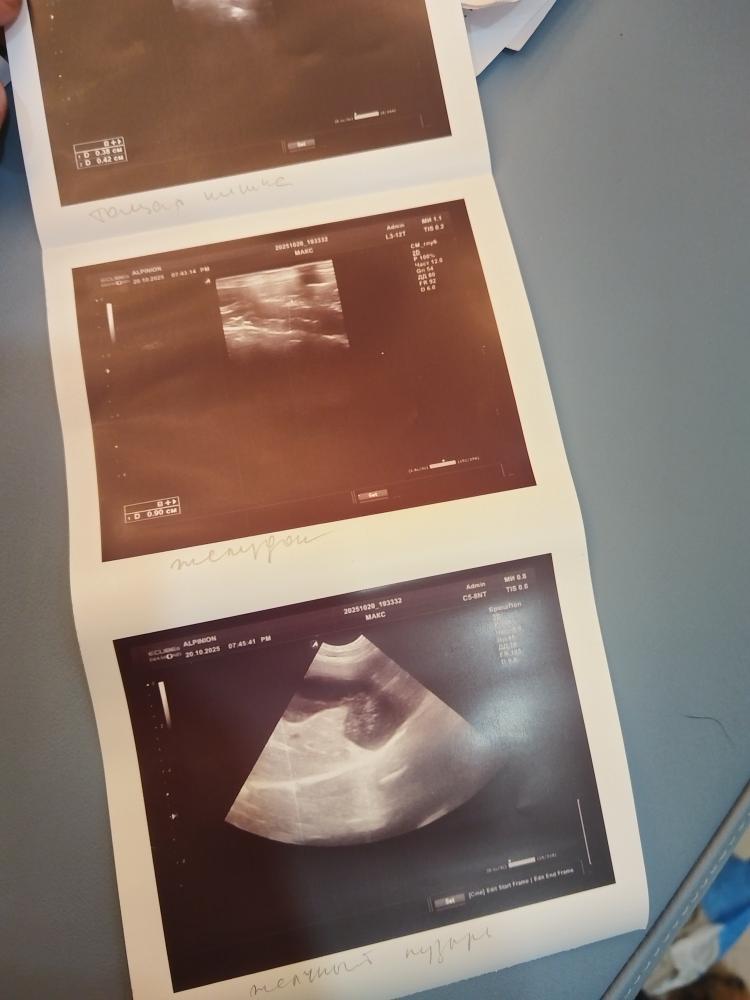

Ну что сказать.

Во отвезёт мне наприключения.

IMG_20251020_200711.jpg.a45a36c69dbb7c5917f08f152a91aa6e.jpg

IMG_20251020_200718.jpg.deca4971444b67601e182735b6da6d7a.jpg

IMG_20251020_200652.jpg.02aa8c8573fa20bfa2d9795c41374083.jpg

IMG_20251020_200656.jpg.9476a0a91506bdd20d3e7e571b001c4a.jpg

IMG_20251020_200703.jpg.4f89f134b55be7a17cbcf0c9ea41e7f0.jpg

Если чумкой переболел, то могут быть неврологические последствия. Типа как у Герды было.

Буду в ближайшие дни сдавать на антитела в Шанс Био.

Сегодня днем небольшой прмтуп без потери сознания, купировался спазганом.

В клинике вел сбея безупречно. На УЗИ заснул